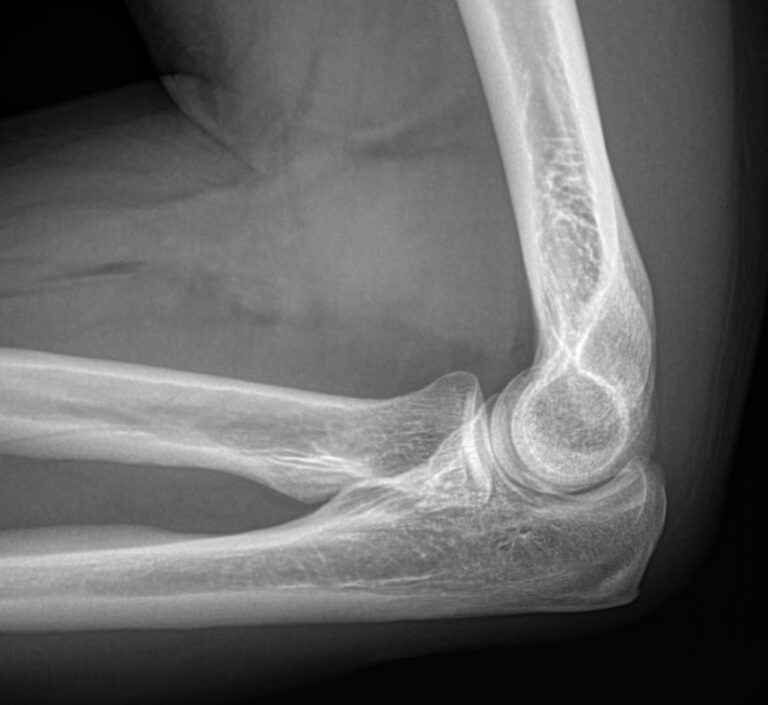

Локтевой сустав считается сложным, он состоит из 3 костей, плечевой, локтевой и лучевой, образующих, соответственно, 3 сустава. Такое строение позволяет свободно двигать рукой и поворачивать ее, обеспечивая достаточный для человека объем движений. Патологии сустава серьезно ухудшают двигательную активность и вызывают болезненные ощущения.

Что покажет рентген локтевого сустава

• Отек мягких тканей;

• Конгруэнтность и состояние суставных поверхностей, например, наличие эрозии и уплотнение суставных поверхностей, а также костные разрастания

• Состояние суставной щели ― сужение, выпот, обызвествление капсулы;

• Структура костной ткани ― типичная, деструкция или участки повышенной плотности и вздутия, остеопения, иные патологии;

• Травмы ― переломы;